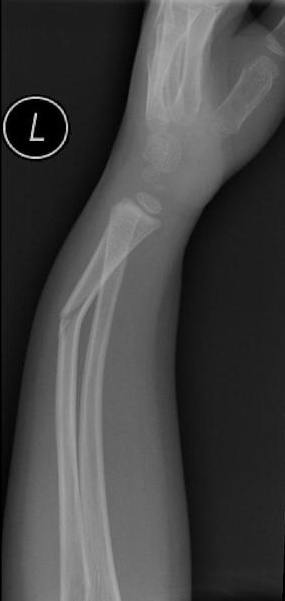

Złamanie typu zielonej gałązki – najczęstszy uraz w wieku rozwojowym

Złamania przedramienia stanowią najczęstszy uraz układu kostnego u dzieci. W codziennej praktyce lekarskiej to właśnie złamanie typu zielonej gałązki (greenstick fracture) pojawia się najczęściej w gabinetach ortopedycznych i na SOR-ach pediatrycznych.

To złamanie niecałkowite, w którym dochodzi do przerwania jednej z korowych warstw kości, przy zachowanej ciągłości po stronie przeciwnej. Elastyczność młodej tkanki kostnej sprawia, że kość nie pęka w pełni – przypomina ugięty, częściowo złamany patyk.

Diagnostyka obrazowa greenstick fracture

Podstawą rozpoznania jest zdjęcie RTG w dwóch projekcjach.

U młodszych dzieci należy wykluczyć urazy wielopoziomowe, a u niemowląt – zawsze rozważyć uraz nieprzypadkowy. W przypadkach wątpliwych pomocne bywa porównawcze RTG drugiego przedramienia.